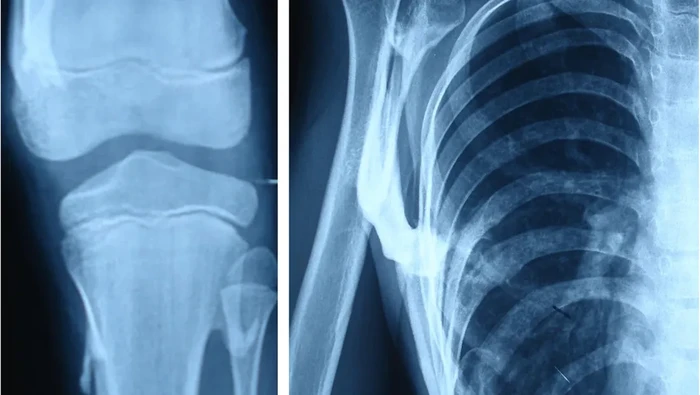

Dalam sebuah studi kasus yang diterbitkan dalam Journal of Medical Case Reports tahun 2019, seorang bocah 10 tahun dilarikan ke rumah sakit akibat benjolan-benjolan menyakitkan di tubuhnya. (Foto: Journal of Medical Case Reports)

Setelah dilakukan pemeriksaan, bocah tersebut menunjukkan gejala klinis dan radiologis dari kondisi fibrodysplasia ossificans progressiva (FOP) atau 'sindrom manusia batu'. (Foto: Journal of Medical Case Reports)

Orang dengan kondisi ini memiliki kelainan yang membuat otot, ligamen, dan jaringan lunak lainnya perlahan berubah menjadi tulang. Akibatnya tubuh terasa kaku seperti 'manusia batu'. (Foto: Journal of Medical Case Reports)

Benjolan-benjolan yang terasa nyeri muncul di punggung akibat massa keras dan kekakuan pada bahu, leher, serta pinggul kiri. Kondisi ini membuatnya juga sulit berjalan atau jongkok secara normal. (Foto: Journal of Medical Case Reports)

Pasien tidak sembuh total, tapi menjalani perawatan konservatif untuk membantu mengurangi perburukan gejala. Pasien sempat menjalani operasi pengangkatan tulang yang tumbuh secara tak normal di pinggul kiri, tapi justru terjadi pertumbuhan tulang yang lebih parah. (Foto: Journal of Medical Case Reports)